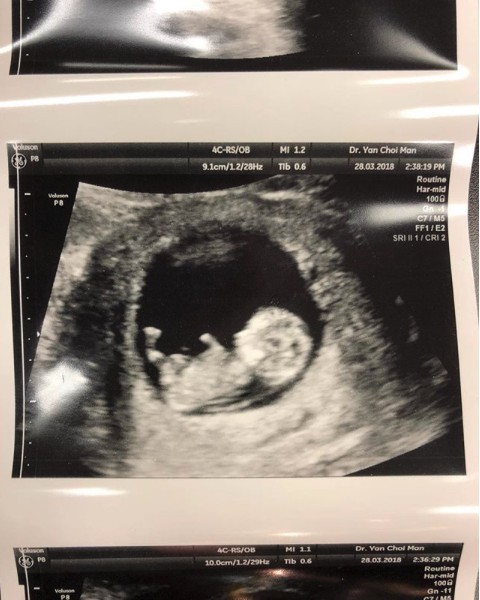

Leanne頭幾個月時,都似有出血跡象,陳柏立即同佢睇醫生,好彩最後食安胎藥就冇事,所以都唔會做啲粗重家務。